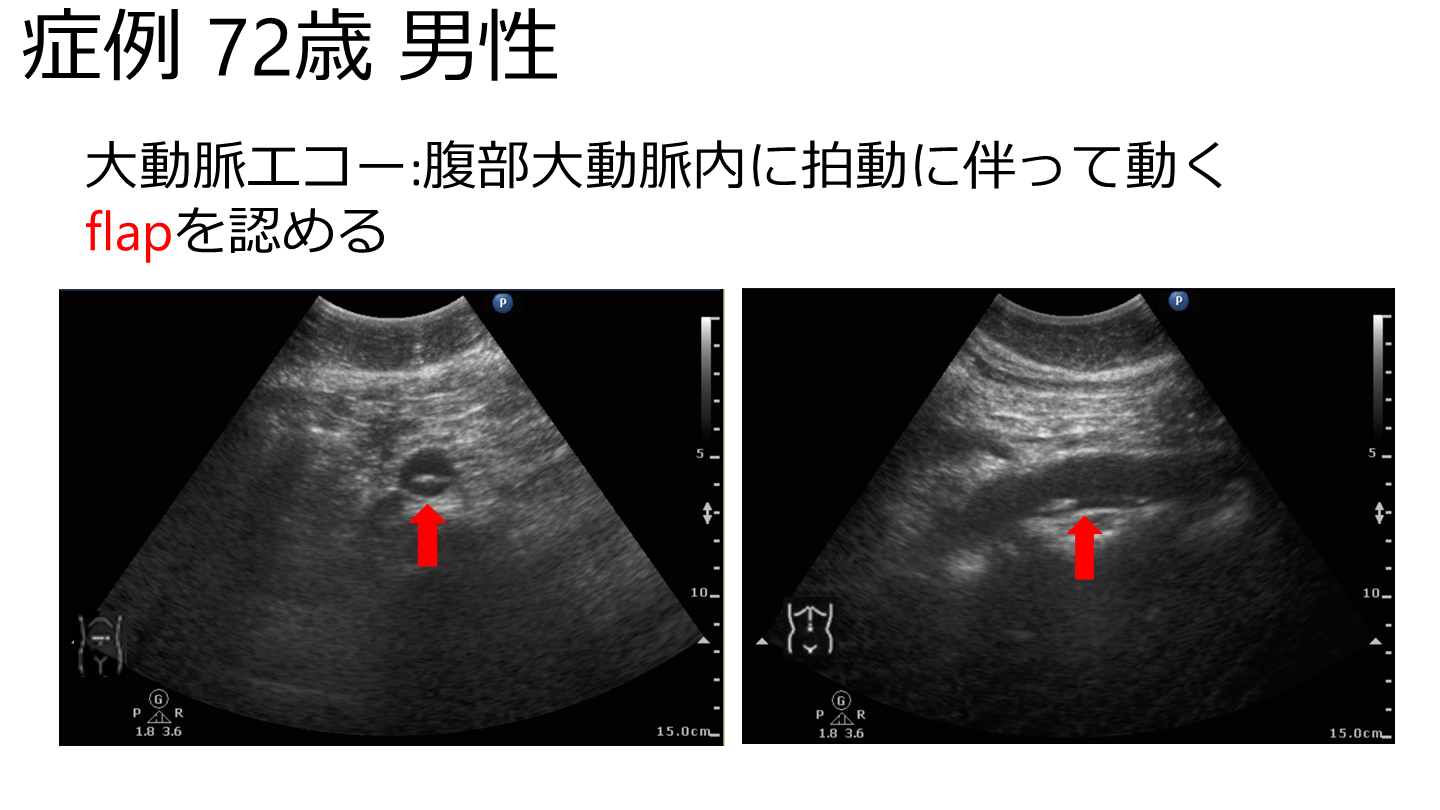

症例 72歳 男性 大動脈エコー:腹部大動脈内に拍動に伴って動くflapを認める

症例 72歳 男性 【経過】 速やかに造影CTを撮影し, Stanford B型急性大動脈解離の診断となる. 降圧, 鎮痛のうえ保存的加療の方針となる. 腹部大動脈瘤/解離を疑えば速やかにエコー →迅速な診断と治療介入につながる